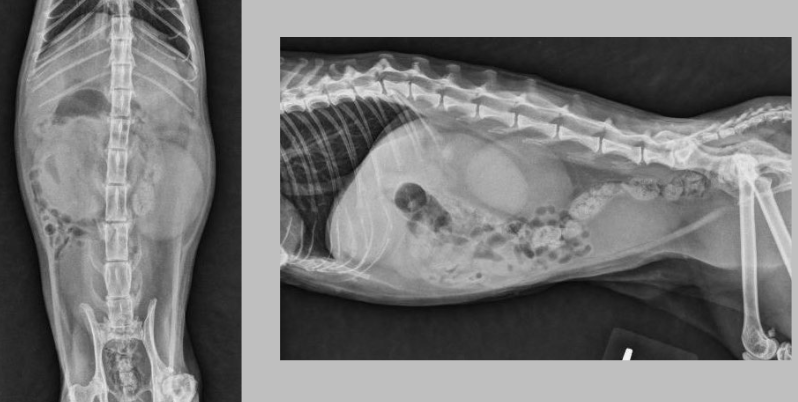

Q

what is going on here?

A

the kidneys, both, are enlarged. this is lymphoma